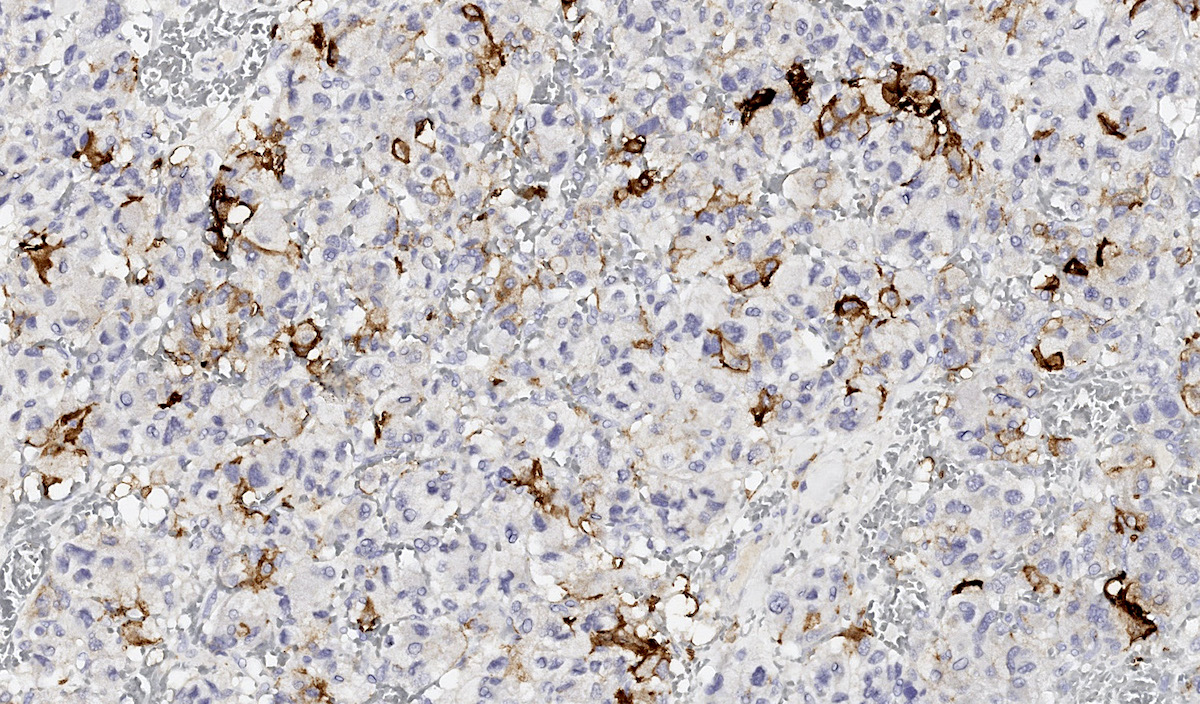

Microscopic (histologic) images

Contributed by Luvy Delfin, M.D. and Sylvia L. Asa, M.D., Ph.D.

Microscopic (histologic) description

- Prevailing histologic pattern: epithelioid chief cells arranged in distinctive clusters / nests (zellballen pattern), separated by prominent fibrovascular stroma (J Clin Med 2018;7:280)

- Trabecular pattern: ribbons or cords of epithelioid cells divided by fibrous bands

- Other patterns: pseudorosette, angioma-like, spindled and sclerosing

- Chief cells: round, oval to polygonal cells with abundant granular basophilic, eosinophilic or amphophilic cytoplasm (Surg Pathol Clin 2019;12:951)

- Intracytoplasmic hyaline globules may be present in sympathoadrenal paragangliomas

- Giant multinucleated cells and bizarre cells can be present (Srp Arh Celok Lek 2002;130:7)

- Rarely, elongated and spindle shaped cells with a sarcomatoid appearance may be found

- Scattered ganglion cells can be seen

- May have nuclear atypia

- May have dysmorphic vessels, melanin-like pigment (neuromelanin) (pigmented paraganglioma), amyloid, abundant stroma and osseous metaplasia (Diagn Pathol 2012;7:77, Hum Pathol 1992;23:33)

- No or rare mitotic figures except in highly aggressive rapidly proliferating lesions

- May have focal chronic inflammatory infiltrate

- Necrosis is unusual except in patients who have undergone preoperative tumor embolization

- Special histopathologic features usually related to genetic syndromes:

- VHL syndrome: prominent stromal edema, clear cytoplasm and lipid degeneration (Am J Surg Pathol 1987;11:480)

- SDHx related syndrome: granular eosinophilic cytoplasm (Am J Surg Pathol 2020;44:422)

- MEN2 syndrome: unilateral or bilateral adrenal medullary hyperplasia (Neoplasia 2014;16:868)